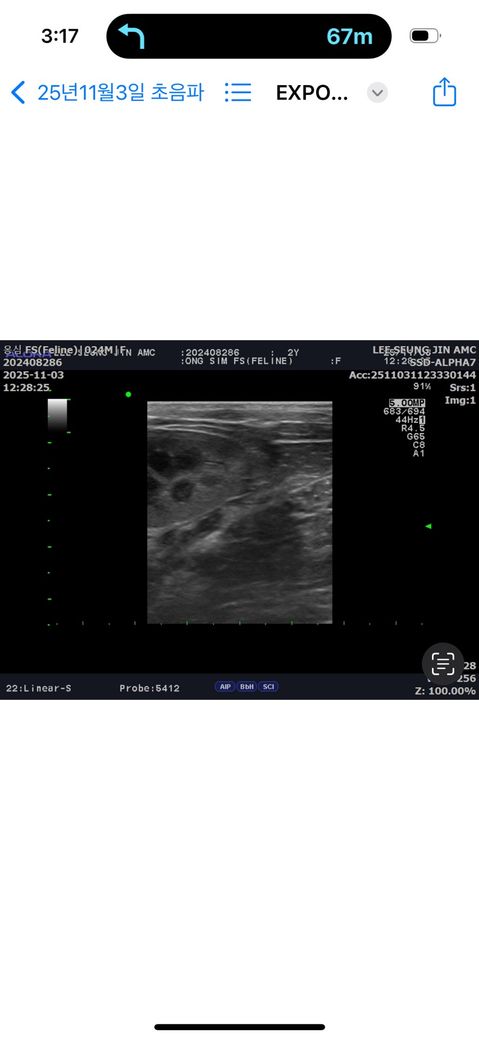

고양이 잔존난소 판정을 받았는데 이런경우는 어떻게 하나요

고양이 여아 1년전에 중성화 수술 했는데 , 발정기 증상 계속 나타나서 수술한병원에 갔는데 자궁 깨끗하게 제거 되어서 잔존난소는 절대 없을거라고 증상 사라지는 경우가 있으니 기다려보자고 하셔서 기다렸는데 2개월에 한번씩 계속 반복이 되서 결국 2차병원가서 잔존난소 판정을 받았어요.. 그동안 애기가 발정으로 받은 스트레스며 , 발정으로 인한 염증같은거 생각하면 짜증나네요 ㅠㅠ 저희도 2개월에 한번씩 새벽에 잠못잔거 생각하면 화도나고 금전적으로도 수술한건데 더 비싼금액으로 수술해야 하는것도 억울하고 더더말고 첫 중성화 수술비나 아니면 새로하는 수술비

청구가 가능한가요 너무 억울해요 ㅠㅠ

말씀하신 상황은 중성화 수술 후에도 발정 증상이 지속되어 잔존난소증후군으로 진단된 경우로 보입니다. 이 질환은 실제로 간혹 발생하며, 보호자 입장에서는 매우 불편하고 억울할 수 있는 상황입니다. 잔존난소증후군은 중성화 수술 시 난소가 완전히 제거되지 못하고 작은 난소 조직 일부가 복강 내에 남거나, 조직이 복막, 인대 등에 유착되어 기능을 유지할 때 생깁니다. 이 조직은 시간이 지나면서 혈류가 다시 공급되어 에스트로겐 을 분비하게 되고, 결과적으로 정상 발정주기처럼 행동 변화, 울음, 교미 자세, 소변 표시 등의 증상이 반복됩니다. 일반적으로 6주~2개월 주기로 반복되는 것은 이러한 호르몬 주기 때문입니다.

수술 중 난소 조직이 남게 되는 원인은 완전히 의료사고라고 단정하기보다는, 난소의 위치 이상, 출혈로 시야가 제한된 경우, 부분적 조직 유착 등 다양한 수술 환경적 요인이 복합적으로 작용하기 때문입니다. 다만, 그럼에도 불구하고 잔존 조직이 생긴 이상 임상적으로는 재수술을 통해 남은 난소 조직을 완전히 제거해야만 증상이 사라집니다. 실제로 잔존난소는 수술 중 난소가 완전히 제거된 것처럼 보이더라도, 미세한 조직이 남아 발생할 수 있어 “불가항력적 합병증”으로 판단되는 경우가 많습니다. 다만, 초진 병원이 당시 적절한 설명을 하지 않았거나, 발정 증상 지속에 대해 정밀검사 없이 단순 경과만 권유한 것이 명백히 부적절한 진료로 판단될 경우에는 일정 부분 책임 소재가 인정될 여지가 있습니다.